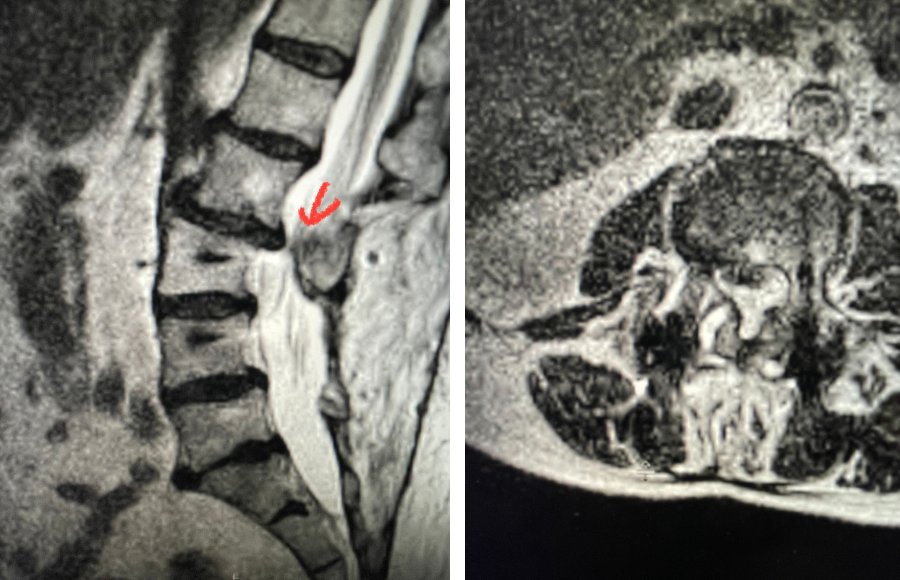

Here is a dramatic example of a patient who had prior laminectomy and fusion surgery four years earlier, and now presents with low back pain with severe burning pain in her right lower extremity pain. She did not respond to epidural steroids. She had a prior L3-S1 laminectomy, and an L3-5 instrumented fusion. A current MRI (Fig 4) demonstrated severe L2-3 next segment stenosis due the development of massively hypertrophied or enlarged L2-3 joint complexes. There was also a grade 1 retrolisthesis of L2 on L3 with a large anterior disc osteophyte complex. The configuration of the stenosis was worse in the right lateral recess secondary to the anterior osteophyte and more right-sided facet compression of the thecal sac, correlating with the patient’s right-sided symptoms. When the anatomy correlates with the patient’s symptoms that is the best set up for success. It was decided to offer a revision surgery to the patient, who agreed.

Fig 4: Sagittal and axial T2-weighted lumbar MRI images demonstrating severe next segment degeneration and stenosis at L2-3 above prior L3-5 fusion. Note retrolisthesis and significant facet arthropathy at L2-3 (red arrow).